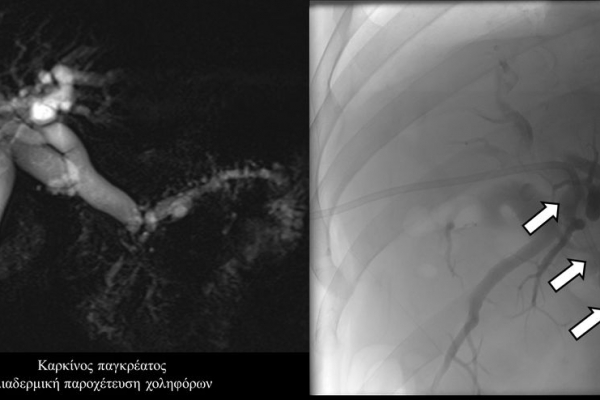

Σε πολλές περιπτώσεις πρωτοπαθών ή δευτεροπαθών όγκων ήπατος - παγκρέατος προκαλείται απόφραξη των χολαγγείων με συνοδό αποφρακτικό ίκτερο.Ο ασθενής με αποφρακτικό ίκτερο δεν μπορεί να υποβληθεί σε χημειοθεραπεία, αν δεν αποκατασταθεί ο ίκτερος με παροχέτευση των χοληφόρων.

Η παροχέτευση των χοληφόρων σε αυτές τις περιπτώσεις θα πρέπει να γίνεται άμεσα, είτε ταυτόχρονα προς τα έξω και προς το 12κτυλο (έσω-έξω παροχέτευση), είτε μόνο προς τα έξω με τη βοήθεια pigtailκαθετήρα (εξωτερική παροχέτευση)

Σε περιπτώσεις όπου υπάρχει απόφραξη των χοληφόρων και ενδείκνυται η τοποθέτηση ενδοπρόθεσης (stent), τότε η βατότητα των χολαγγείων και η αντιμετώπιση του αποφρακτικού ικτέρου μπορεί να διασφαλιστεί με την τοποθέτηση ενδοπροθέσεων (stents).

Η προσπέλαση σε όλες τις περιπτώσεις γίνεται διαδερμικά και η νοσηλεία του ασθενούς διαρκεί συνήθως μία ημέρα και ο ασθενής επιστρέφει στο σπίτι του την επομένη.